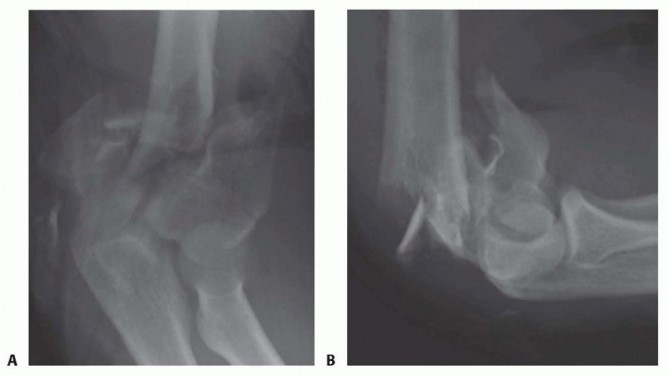

Plain radiographs, including anteroposterior (AP) and lateral views ( FIG 2) of the elbow and both wrists, should be obtained. The elbow view may have to be taken in a protective splint or plaster backslab for patient comfort.Elbow radiographs will allow initial assessment of the degree of comminution and may indicate the presence of decreased bone mineral density.Bilateral wrist views will indicate the presence of an axial (interosseous membrane) injury if the ulnar head is in positive variance compared to the contralateral uninjured wrist.Plain tomograms are of use in improving the understanding of the fracture configuration, but an alternative would be a computed tomography (CT) scan. With the latter, the surgeon can view a three-dimensional reconstruction, which is a useful surgical planning tool for ORIF.If there is evidence on physical examination of a neurologic injury, it is prudent to document its extent with a carefully performed neurologic examination.

FIG 2 • Standard AP (A) and lateral (B) plain radiographs.